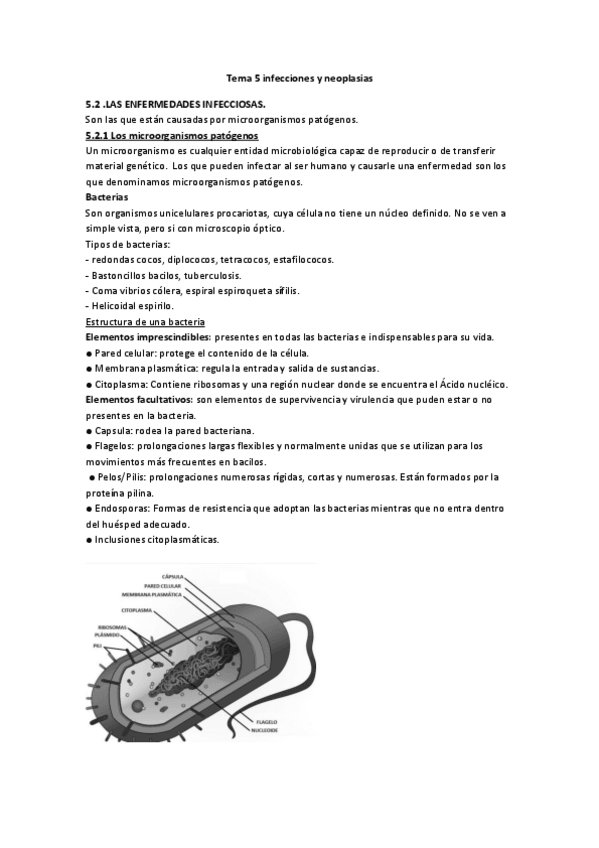

He publicado nuevos apuntes de Fisiopatología general: Tema-5-infecciones-y-neoplasias.pdf